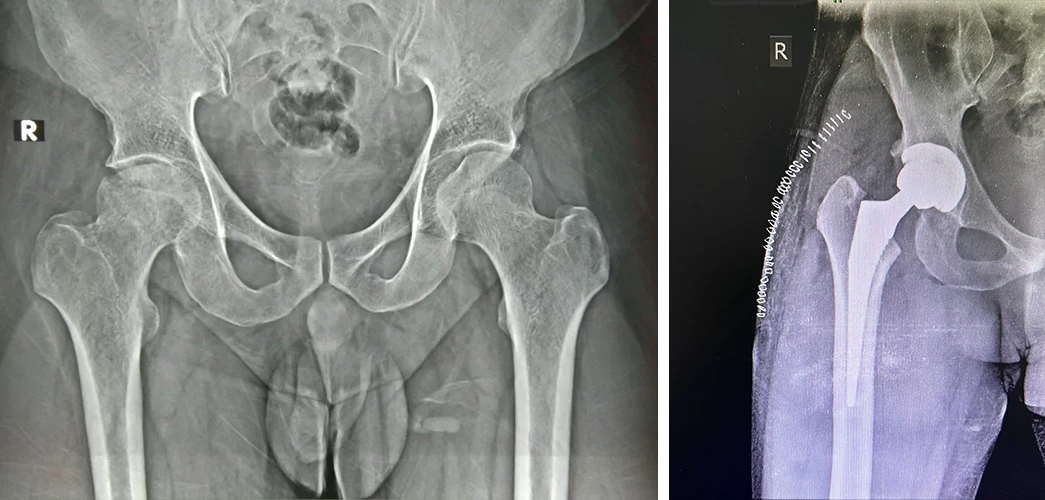

Total Hip Replacement

Are your hips causing you constant discomfort? If you're tired of living with hip pain, Dr. Prasun Sanyal is your best solution.

My mother had hip fracture in 2018. We consulted Dr. Sanyal through a recommendation from my neighbour. My mother was operated for Hip Replacement. Immediately after surgery she was allowed to stand.

Dr. Sanyal thoroughly followed up in post op & he was accessible for any query of us. My mother visited Kamakhya Temple in 2020 climbing all stairs. 5 years down She is absolutely fit & living a normal life. My heartfelt gratitude to Dr. Sanyal for his exceptional care & compassionate attitude